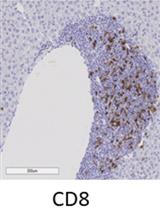

The ability to assess the function of a range of cytokine, antigen receptor, and Toll-like receptor (TLR) signaling pathways in a range of immune cells could provide a kind of fingerprint of the state of the human immune system. The mass cytometry or CyTOF, platform allows for the parallel application of about 40 labeled antibodies to a single sample, creating the possibility to read out many cell types and signaling pathways in a single small blood sample. We developed such a mass cytometry panel, consisting of 22 antibodies to cell surface lineage markers and 8 antibodies to phospho-specific epitopes of signaling proteins. These antibodies were chosen to discriminate all major white blood cell lineages, to a level of detail that includes subsets such as naïve, central memory, effector memory, and late effector CD4+ and CD8+T cells, naïve, transitional, and switched memory B cells, plasmablasts, myeloid and plasmacytoid dendritic cells, CD16+ and CD16+CD56+ NK cells, CD16+ and classical monocytes etc. 32 such cell subsets are defined in our standard gating scheme. The eight phospho-specific antibodies were chosen to represent major signaling nodes responsive to cytokine, TLR, and antigen receptor signaling. This antibody panel is used with 8 standard stimulation conditions (unstimulated, IFNa, IL-6, IL-7, IL-10, IL-21, LPS, PMA+ ionomycin), although other stimuli can be added. Comparison of healthy controls to subjects with immune deficiencies of unknown etiology may help elucidate the mechanisms of such deficiencies.